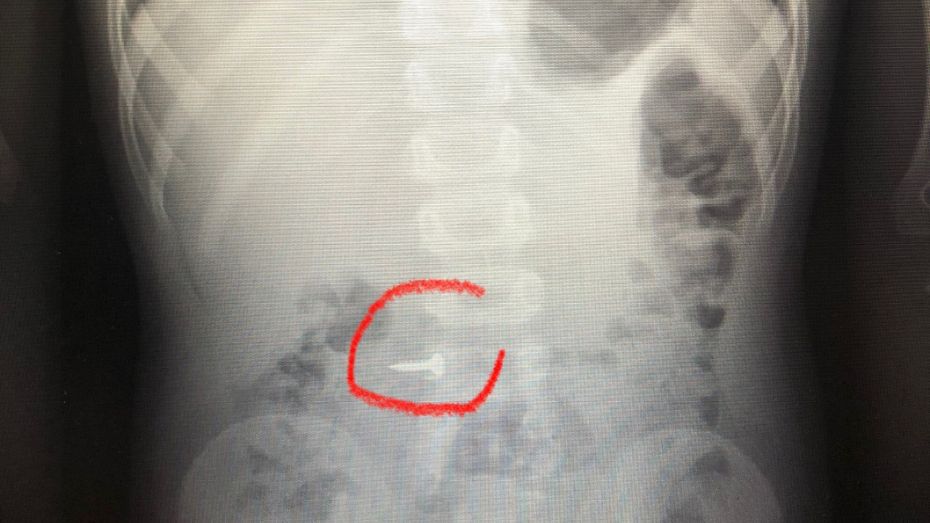

Врачи областной детской клинической больницы №2 в Воронеже поделились рентгеновскими снимками детей, которые проглотили шуруп, гайку или другие инородные предметы. Фото опубликовали в соцсети учреждения в понедельник, 19 июня. Медики отметили, что количество обращений в приемное отделение с жалобой на возможное проглатывание ребенком инородного тела не снижается.

– Батарейки, монеты, иголки, магниты не должны попадать в руки детям! Нужно также следовать правилу: «маленькие дети – большие игрушки», – подчеркнули медики.

Ранее РИА «Воронеж» рассказывало, что врачи спасли ребенка, который проглотил канцелярскую кнопку. Юному пациенту провели операцию, чтобы удалить инородное тело.